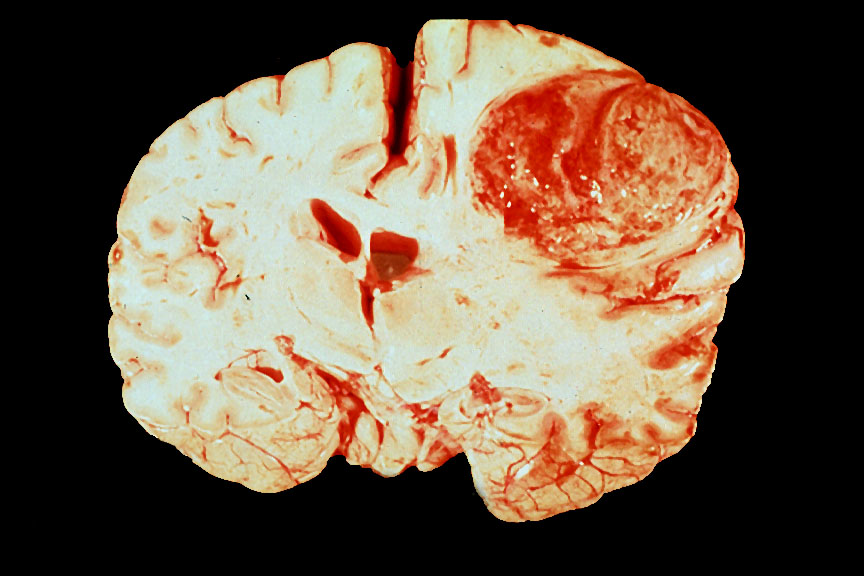

Brain, gross, Glioblastoma multiforme, frontal lobe

Glioblastoma multiforme of the frontal lobe in a 60 year old woman. The tumor is multicolored (red and brown for recent and old hemorrhages, and yellow areas of necrosis).